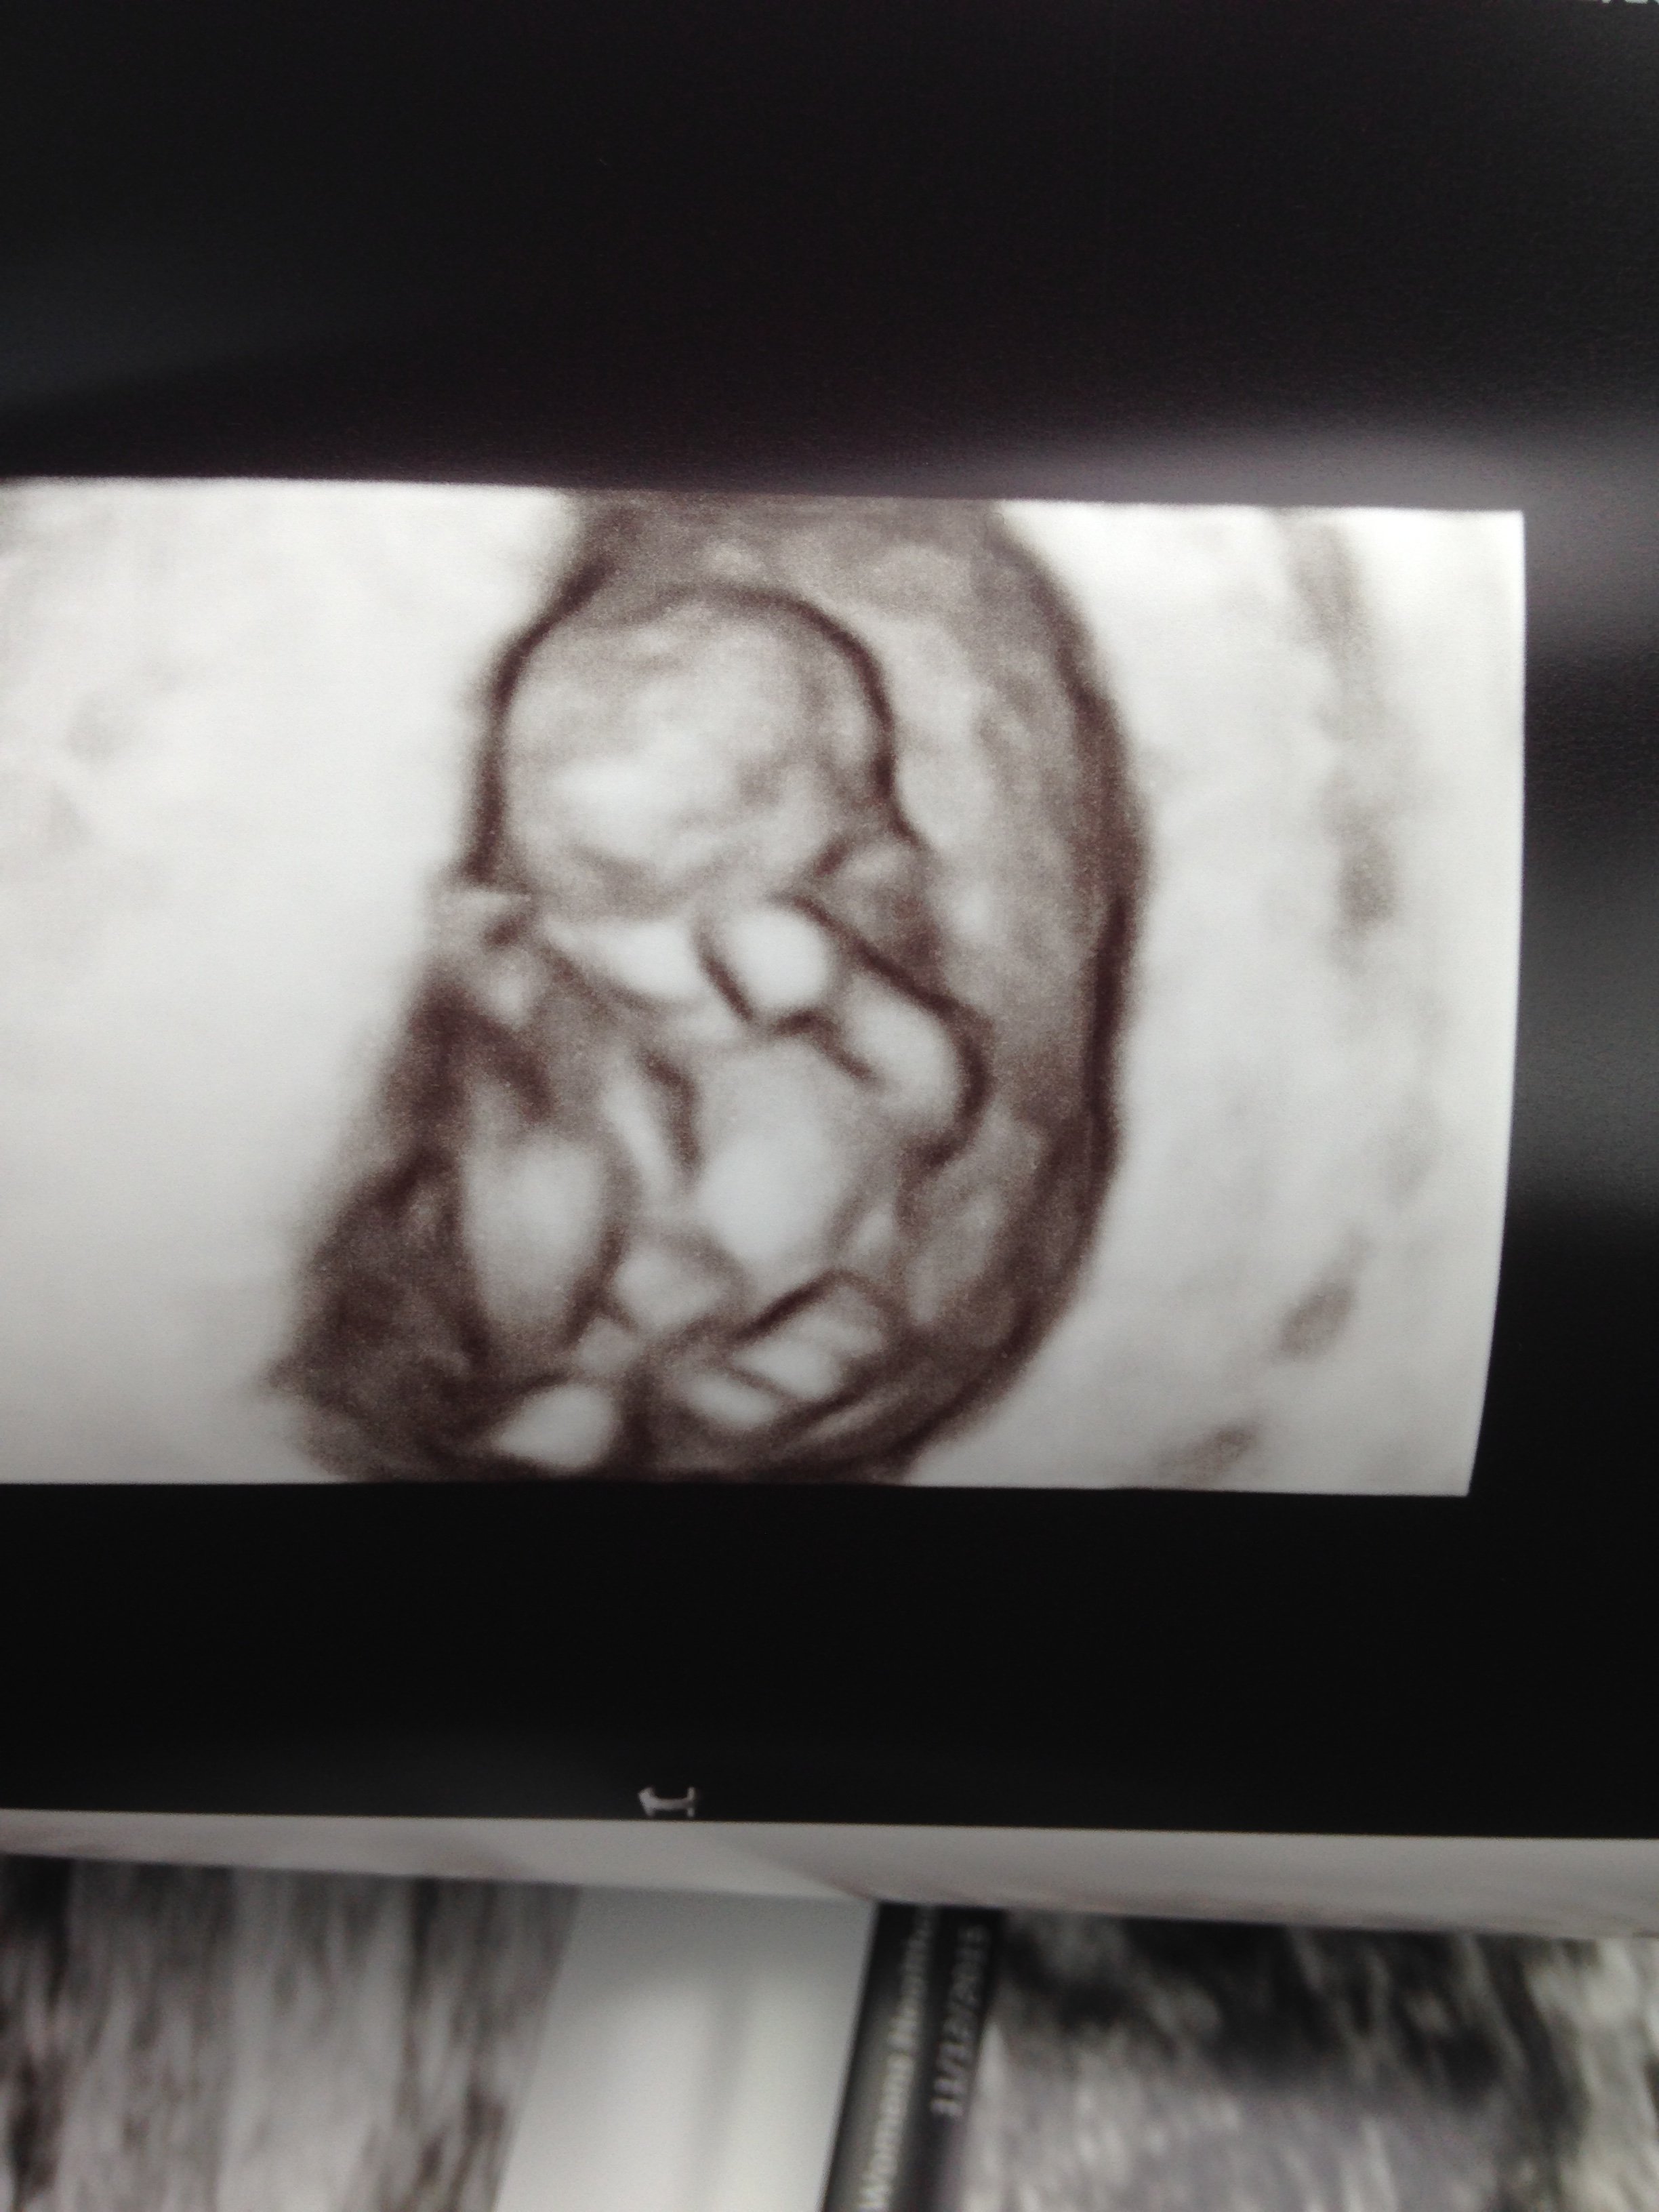

Today was my first ultrasound! I feel so relieved now that everything went well. I'm measuring as I should be. I'm 10w1d. The baby's heart beat was 163! I'm so in love! I can't stop looking at my pictures. I also got to see 3D and it was amazing. Feels so much more real now! I'll have to wait I guess to post my pic